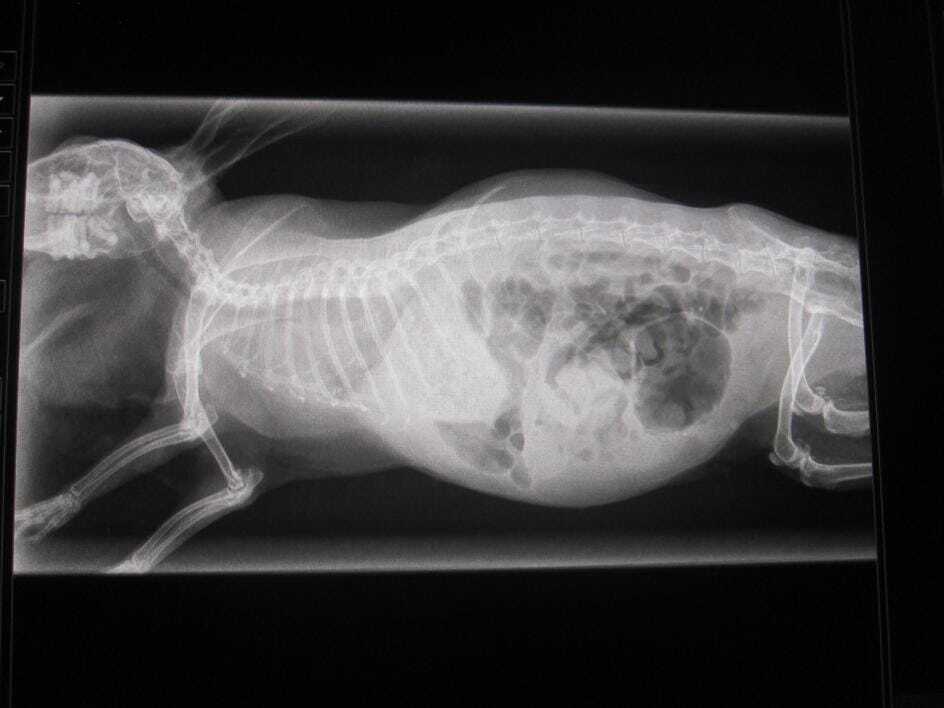

Where an obstruction is suspected, it is useful to check a blood glucose level. Rabbits that have very high blood glucose when in gut stasis are more likely to have a gut obstruction, although this is not diagnostic. If the blood glucose is high, then X-rays (Figures 1 to 3) or ultrasound should be used to further rule in or out an obstruction.